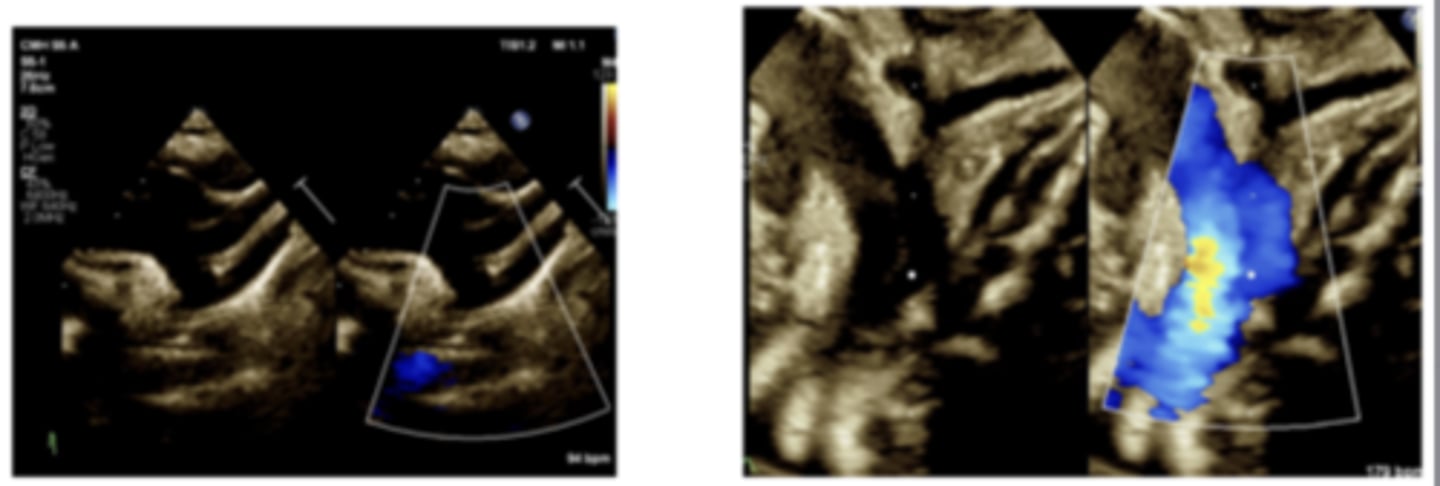

Aortic Stenosis

WHAT LESION?

critical AS